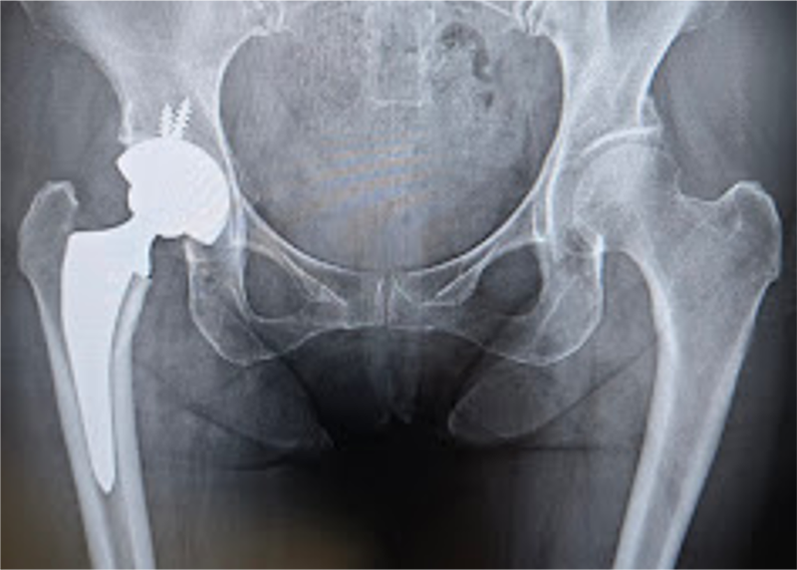

〈手術後のレントゲン〉(正面)

〈手術後のレントゲン〉(側面)